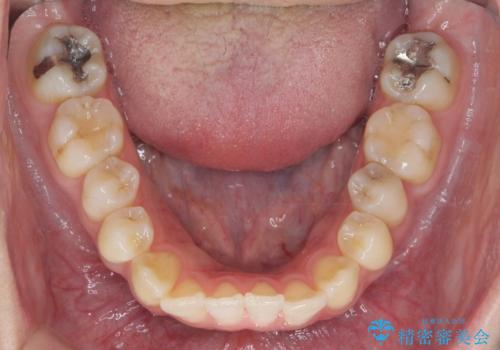

引っ込んだ前歯を並べたい マウスピースと部分ワイヤーのコンビネーション矯正

- 引っ込んで生えてしまっている前歯を並べたい、と矯正治療を希望され来院されました。

まずマウスピース矯正インビザラインシステムで、引っ込んだ歯が並ぶためのスペースを作ったのち、部分ワイヤー矯正を行い短期間での配列を計画します。

このように前歯の部分ワイヤーは引っ込んでしまった前歯や がたつきを素早く改善することができます。